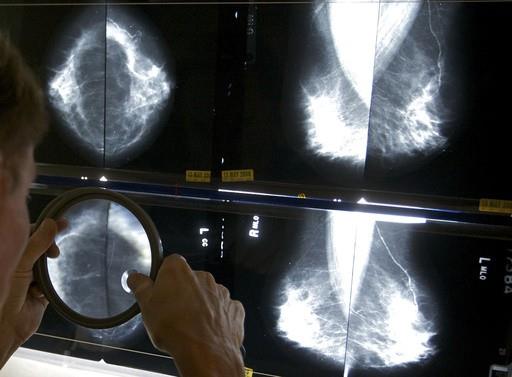

Aproximadamente la mitad de las mujeres mayores de 40 años tienen mamas densas, con menos tejido adiposo y más tejido conjuntivo y glandular. Ese tejido aparece blanco en las radiografías, del mismo color que los tumores mamarios, lo que dificulta la lectura de las mastografías. El tejido mamario denso es uno de los factores que puede aumentar las probabilidades de que una mujer desarrolle cáncer.

Según las nuevas normas, las mujeres con mamas densas recibirán una nota escrita alertándolas de que su estado “dificulta la detección del cáncer de mama”. También se les indicará a esas pacientes que discutan los resultados con su médico.